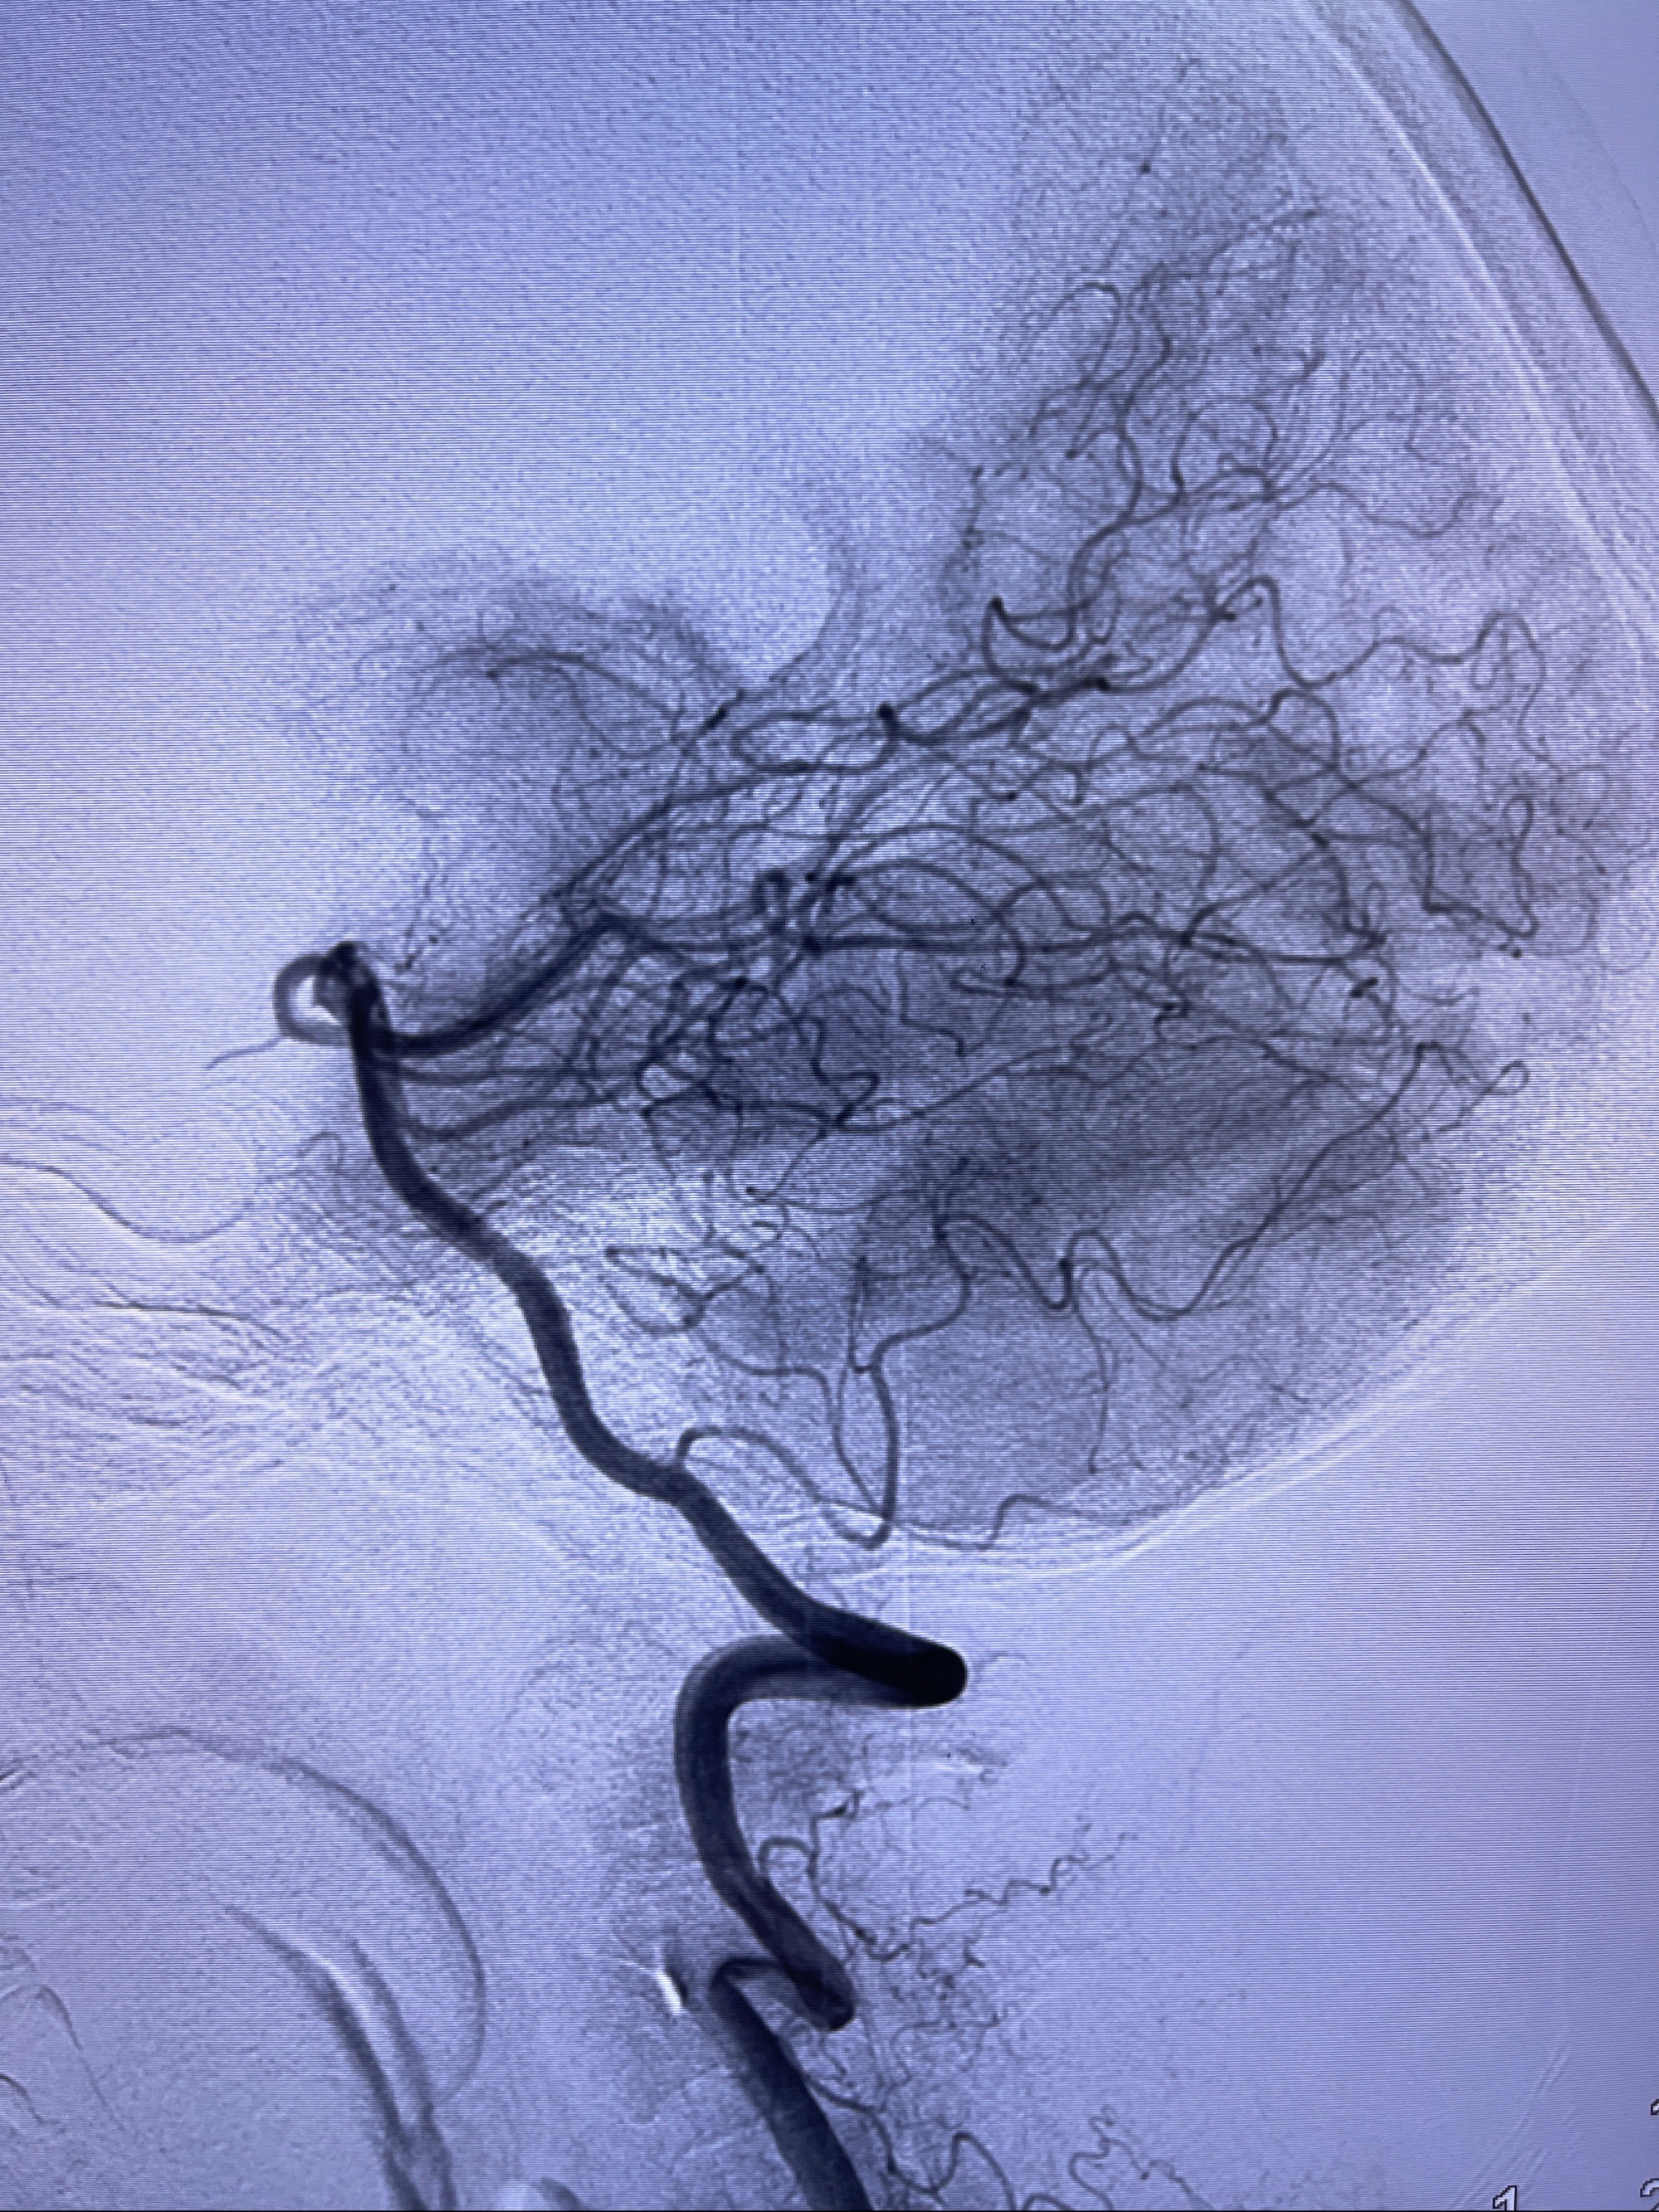

2023-08-30DSA:左侧颈内动脉眼动脉动脉瘤,约3*9.2*7.3mm大小

2023-09-06全麻下行左侧颈眼动脉瘤

密网支架辅助栓塞

术后3D显示支架贴壁佳

麻醉苏醒佳,遵嘱活动!视力视野正常。